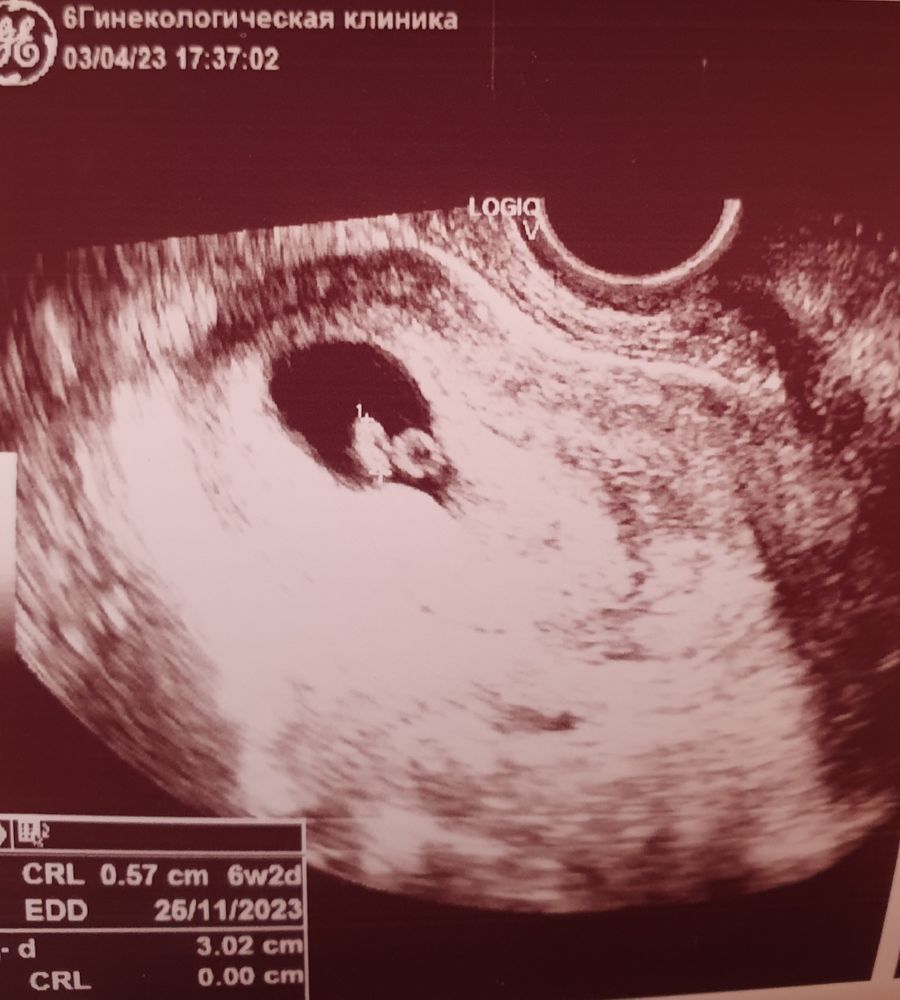

В клинике работал бесперебойник, к которому видимо были подключены аппараты узи. Врач приняла меня. Всё оказалось хорошо. Увидели эмбриончик и послушали сердечко. Врач сказала, что никаких отслоек, полипов или гематом нет, выделения скорее всего из второго рога, так как эндометрий там выглядит так, как будто вот-вот начнутся месячные.

ПЯ 28 мм, ЖМ 3,2 мм, КТР 5,7 мм, ЧСС 127.

Срок по последним месячным 7 недель и 2 дня, срок по узи - примерно 6 недель и 2 дня из-за поздней овуляции.